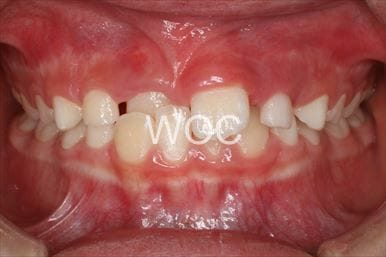

八重歯・叢生上のみ舌側矯正、下はエッジワイズ装置

上は舌側矯正を希望。ガタガタ(叢生)が強い。上顎右側中切歯・側切歯が歯科治療で連結してあったがそれを除去してから治療開始しました。

- 年齢:23歳女性

- 主訴:上下前歯のガタガタが気になる

- 基本矯正料金:103万円

- 治療期間:2年2ヶ月

- 非抜歯